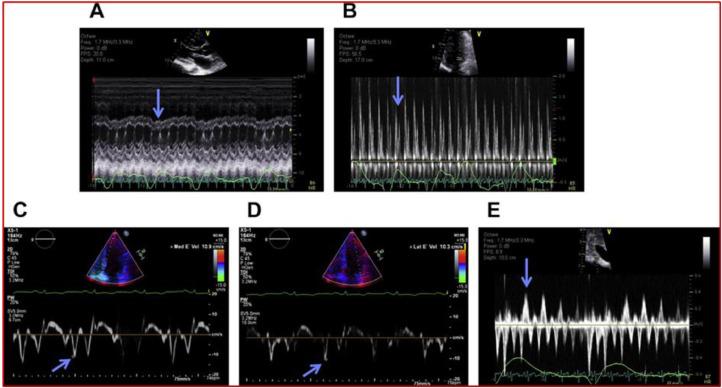

Chronic constrictive pericarditis is a pericardial affection that causes a severe impairment of myocardial compliance. Among its many etiologies, tuberculosis is the most common cause, mainly in developing countries. Multimodal imaging methods are essential tools for guiding diagnosis. We present the case of a 64-year-old man with no past medical history who presented with dyspnea stage II of NYHA and right heart failure. At admission, he was stable, with normal blood pressure and a normal heart rate. His ECG showed a low voltage of QRS complexes. Transthoracic echocardiography revealed significant pericardial thickening enveloping the ventricles, with significant respiratory flow variation. A thoracic CT scan and cardiac MRI confirmed the presence of pericardial thickening and calcifications. The patient underwent beat-heart pericardial decortication. The anatomopathological examination of the surgical piece revealed Mycobacterium tuberculosis. The postoperative check-up after 6 months showed good clinical and echocardiographic evolution.

慢性缩窄性心包炎是一种导致心肌顺应性严重受损的心包疾病。在其众多病因中,结核病是最常见的病因,主要发生在发展中国家。多模态成像方法是指导诊断的重要工具。我们报告一例64岁男性患者,既往无病史,出现纽约心脏协会(NYHA)II级呼吸困难和右心衰竭。入院时,他病情稳定,血压正常,心率正常。他的心电图显示QRS波群低电压。经胸超声心动图显示心室周围心包显著增厚,伴有显著的呼吸血流变化。胸部CT扫描和心脏磁共振成像证实存在心包增厚和钙化。患者接受了心脏不停跳心包剥脱术。手术标本的解剖病理学检查发现结核分枝杆菌。6个月后的术后检查显示临床和超声心动图有良好的进展。